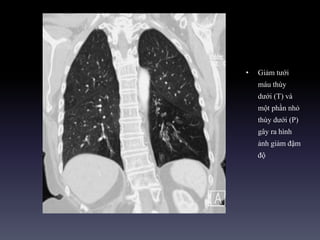

• Giảm tưới

máu thùy

dưới (T) và

một phần nhỏ

thùy dưới (P)

gây ra hình

ảnh giảm đậm

độ